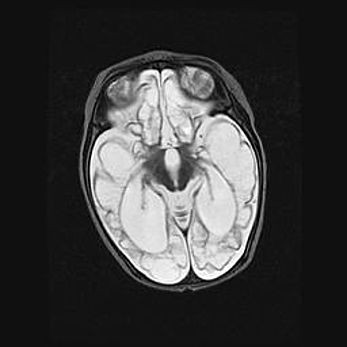

Церебральная ишемия II.

Возраст: 5 дней

Вес: 3400 г

Пол: женский

Окружность головы: 35 см

Срок гестации: 39 недель

Церебральная ишемия – это заболевание, характеризующееся недостаточностью (гипоксией) либо полным прекращением (аноксией) снабжения мозга кислородом по причине закупорки одного или нескольких сосудов. Это приводит к  что метаболическим расстройствам различной степени тяжести в тканях головного мозга, развитию коагуляционных некрозов и гибели нейронов.